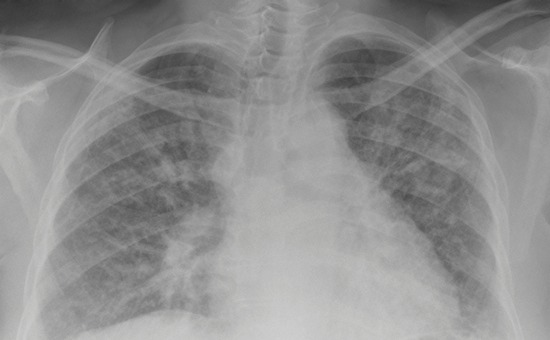

Respiratory issues affect more than one in four Australians and 14 per cent of all deaths in Australia are caused by a lung disease-related illness.

More than 10% of health issues in Australia relate to lung issues

One in seven people in Australia die of a lung disease-related illness

Fibrosis causes disability and death to millions of people affected by this respiratory disease each year. At present, many treatments are limited and an improved understanding of the factors that drive fibrosis is needed to improve treatment. This project looks at how cells communicate to initiate and drive fibrosis, while drug testing new ways to alter cell communication to stop the disease. The aim of the project is to develop a new method of treating fibrosis patients that is more effective than past treatments.

There is currently no cure for Idiopathic pulmonary fibrosis (IPF).Researchers in this project believe IPF develops because the normal mechanisms in the myofibroblasts (the cells that produce the connective tissue) don’t work, and this causes too much connective tissue, which leads to the oxygen stopping from getting into the blood. The team has identified a protein it believes could cause the mechanism in the myofibroblasts to work as normal, which could potentially cure pulmonary fibrosis.

Asthma is one of the most common reasons children need emergency medical treatment in Western Australia. Our research program involves studying young children during the peak of their asthma attack. Studying children at this time with a follow-up on recovery is the best way to discover the underlying causes of asthma. Most attacks are due to viruses and we use the latest and most powerful biological technologies to discover how viruses cause serious wheeze. These technologies include assessing viruses, genetic susceptibility, immune system responses, metabolic responses, changes in the microbiome and the effect of treatment on each of these.

A new study carried out by The University of Western Australia, the Busselton Health Study and Sir Charles Gairdner Hospital has found Vitamin D deficiency can contribute to poor respiratory functioning and health in middle-aged adults.